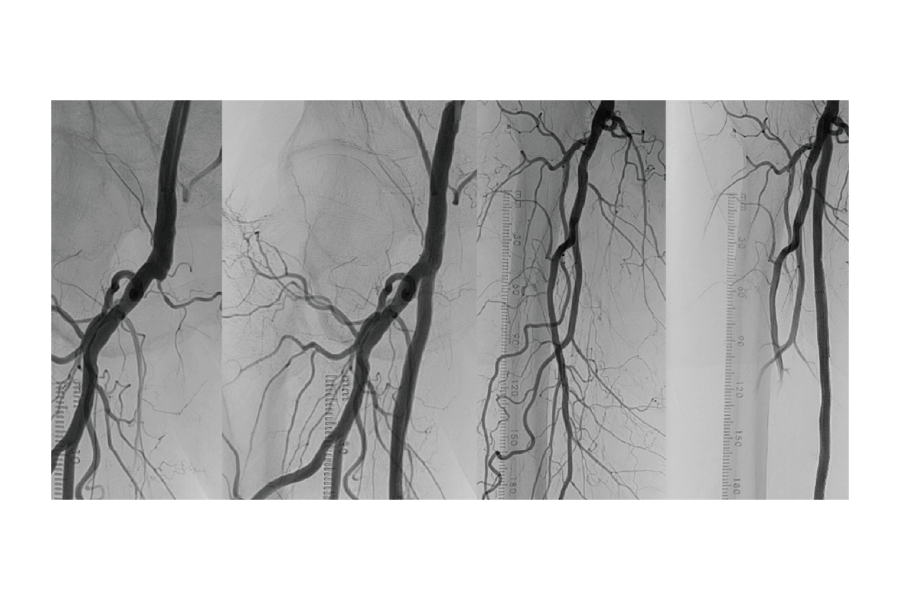

末梢血管疾患の中で、特に下肢閉塞性動脈硬化症は進行した動脈硬化疾患で、高齢、高血圧、コレステロール、糖尿病、喫煙などの生活習慣病が原因です。年々患者数は増え続けており、最終的に下肢切断となったり、場合によっては亡くなることもあります。

しかし近年では、血管内の治療技術が進歩し、高い成功率と一度治療したところが再度狭くならない「高い開存率」を得られるようになりました。そして私は、治験や国内外の医師との仕事の経験を活かして、当院でもこの治療ができる環境を作り上げました。看護師、臨床工学技士、放射線技師、フットケアチームと共に、包括的な治療を

行ってまいります。また、これまで薬剤治療のみに限定された深部静脈血栓症※に対する先進的なカテーテル治療ができるようになりました。当院では、現在国内で15〜20施設のみに限定されたこの治療が受けられます。

■大腿動脈の血栓閉塞